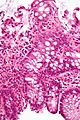

Cryptitis in a rectal biopsy. H&E stain.

Cryptitis is inflammation of an intestinal crypt.

- Intestinal crypts with intraepithelial neutrophils.